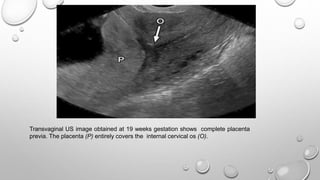

Transvaginal US image obtained at 19 weeks gestation shows complete placenta

previa. The placenta (P) entirely covers the internal cervical os (O).

PLACENTA PREVIA

 Placenta previa refers to abnormal implantation of the

placenta in the lower uterine segment, overlying or near the

internal cervical os

 Normally, the lower placental edge should be at least 2 cm

from the margin of the internal cervical os.

 The diagnosis of placenta previa should not be made before

15 weeks gestation.